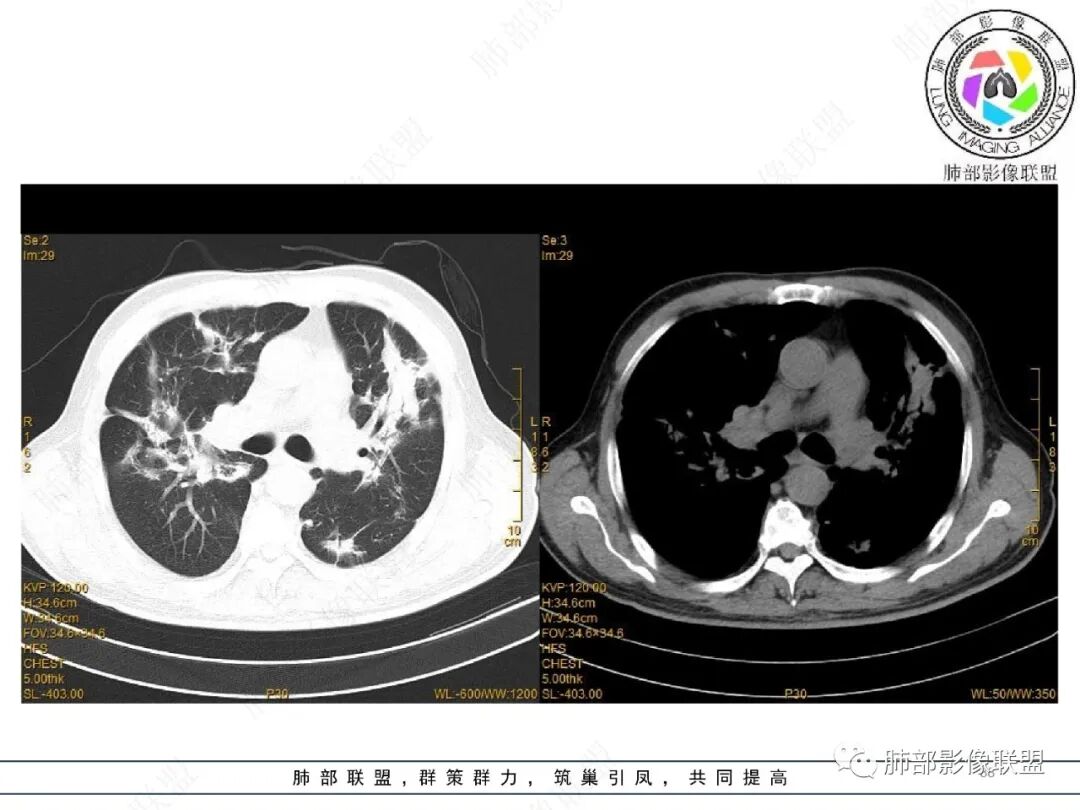

2022.2.17CT显示两肺中内带多发结节影、斑片影、条索影,部分病灶侧向融合与胸膜平行。部分病灶沿着支气管血管束分布、其内支气管稍扩张。部分病灶呈反晕征。大部分病灶边界显示清晰,部分病灶周围可见边界不清的GGO。2022.4.12CT显示两肺中内带多发结节影、条索状、条带状高密度影,边界收缩平直凹陷,大部分病灶沿着支气管血管束分布,亦有位于胸膜下侧向融合与胸膜平行的病灶。总体与第一次CT对比两肺病灶明显吸收。